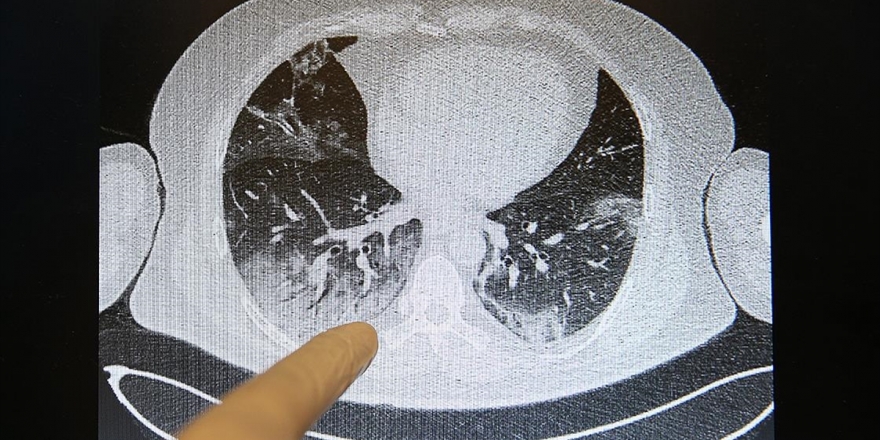

Kovid-19'un Akciğerlere Verdiği Zarar Tomografi Görüntülerine Yansıyor